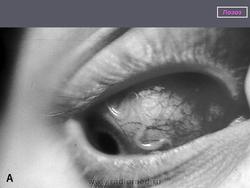

Перемещение червей под кожей вызывает зуд и жжение, передвижение их в уретре приводит к сильнейшим болям. Проникший под конъюнктиву паразит вызывает отек и гиперемию конъюнктивы, отек век, что нередко сопровождается сильной болью в глазу. Особенно опасные симптомы развиваются в связи с массовой гибелью микрофилярий, например при лечении. Отмечаются поражения почек с нефротическим синдромом, синдром менингоэнцефалита. Гибель зрелых паразитов и вторичная инфекция могут повлечь за собой развитие абсцессов различной локализации.

После внедрения возбудителя в организм человека в типичных случаях возникают общие аллергические симптомы: лихорадка, крапивница, зуд кожи, парестезии, которые вскоре купируются. Через 1-3 года развиваются характерные признаки лоаоза: «калабарский отек», подкожная и внутриглазная миграция зрелых гельминтов и гиперэозинофилия. Самым постоянным, обычным симптомом являются преходящие, ограниченные на разных участках туловища и конечностей отеки в виде куриного яйца или укуса осы, безболезненные; кожа над ними не изменена.